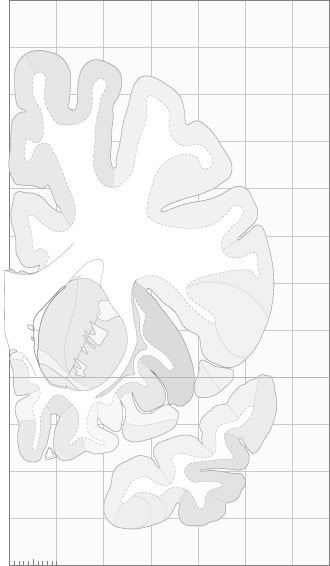

Frontal sections (Nissl) from the Atlas Brain:

Slice

Macroscopy

Schematic

Slice ID:

r2-0545

Plate NR:

10-11

Position:

-18,5 mm